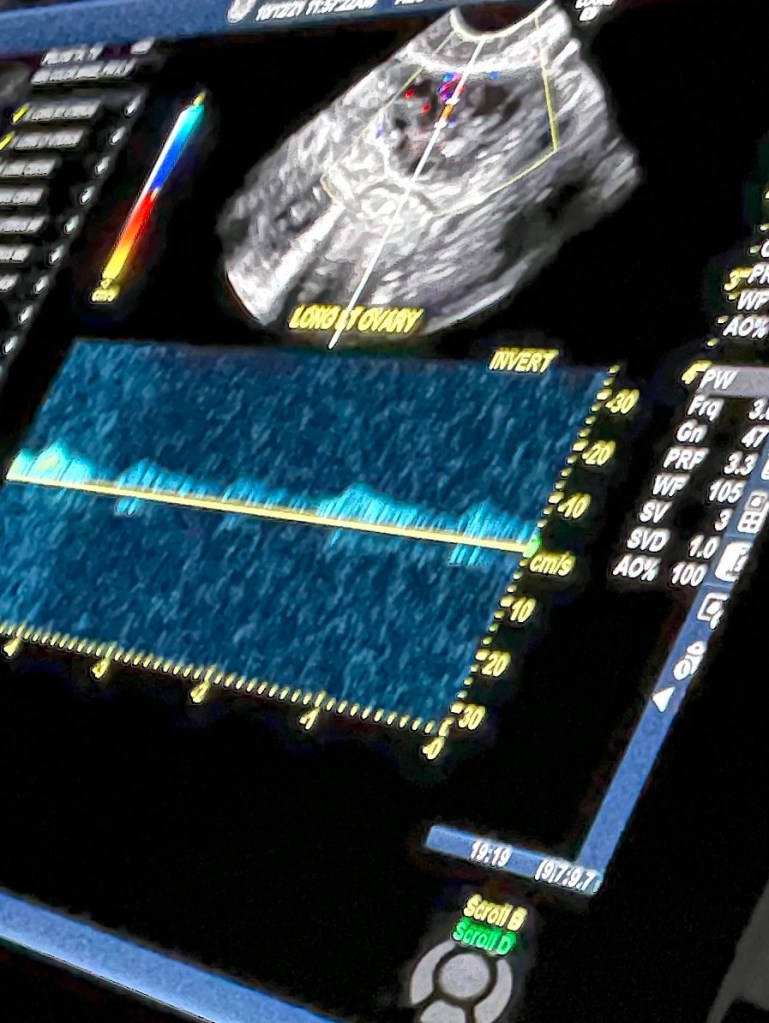

I went back to my room pale and in shock. I told my boss I had to go cause I was bleeding. She said go its fine I will figure something out. I clocked out went to my car and drove to the walk in. I talked to the nurse and she said I need to go to the ER due to me being in first trimester. I went to ER. Got checked in. They did blood work. Once I saw the doctor she said listen I don’t know what I am doing in this situation, you are my first pregnant man I’ve seen. I am going to run some tests and then send the results to your doctor for a diagnosis. Shortly after I saw the doctor my boyfriend got there. Next I had an ultrasound and a vaginal ultrasound, papsmeer, and pelvic exam. They diagnosed me with an enlarged uterus and inter utero bleeding. The next day I heard from my doctor she said you had a miscarriage at approximately 8 weeks. I was heart broken and angry.